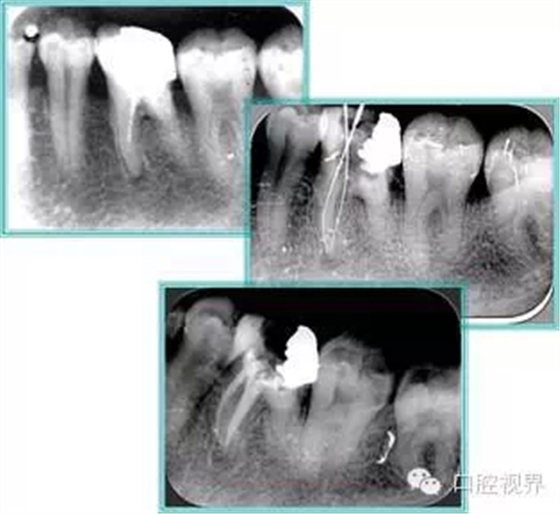

共有 4 張 X 線片,分別是術(shù)前、診斷絲 、主牙膠尖確認(rèn)、術(shù)后。

( 1 )術(shù)前:術(shù)前 X 線片用來(lái)了解牙齒的大概情況。術(shù)前預(yù)期為多根牙時(shí) X 線片應(yīng)偏頭拍攝。

( 2 )診斷絲:根據(jù)術(shù)前 X 線片進(jìn)行開(kāi)髓、根管的初步預(yù)備后,需要插入診斷絲,用來(lái)指示工作器械位置。常用 10 號(hào)或 15 號(hào)擴(kuò)大器作為診斷絲插入牙髓腔。

( 3 )主牙膠尖確認(rèn):通過(guò)術(shù)前預(yù)期和診斷絲診斷,明確工作長(zhǎng)度、牙根走向,進(jìn)行根管預(yù)備。之后應(yīng)進(jìn)行主牙膠尖(中銼)確認(rèn),已明確根管是否適合充填。

( 4 )術(shù)后:觀察治療效果。